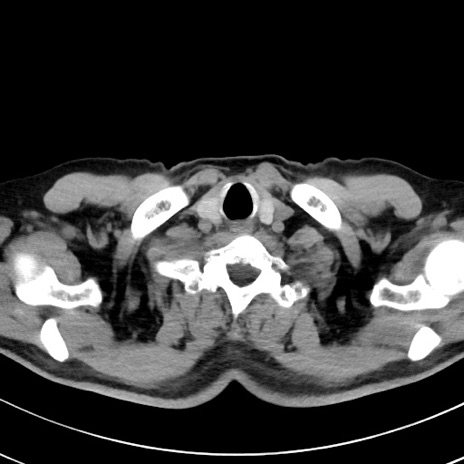

【腹部TIPS】症例29 参考症例 CT(横断像)

症例

70歳代男性